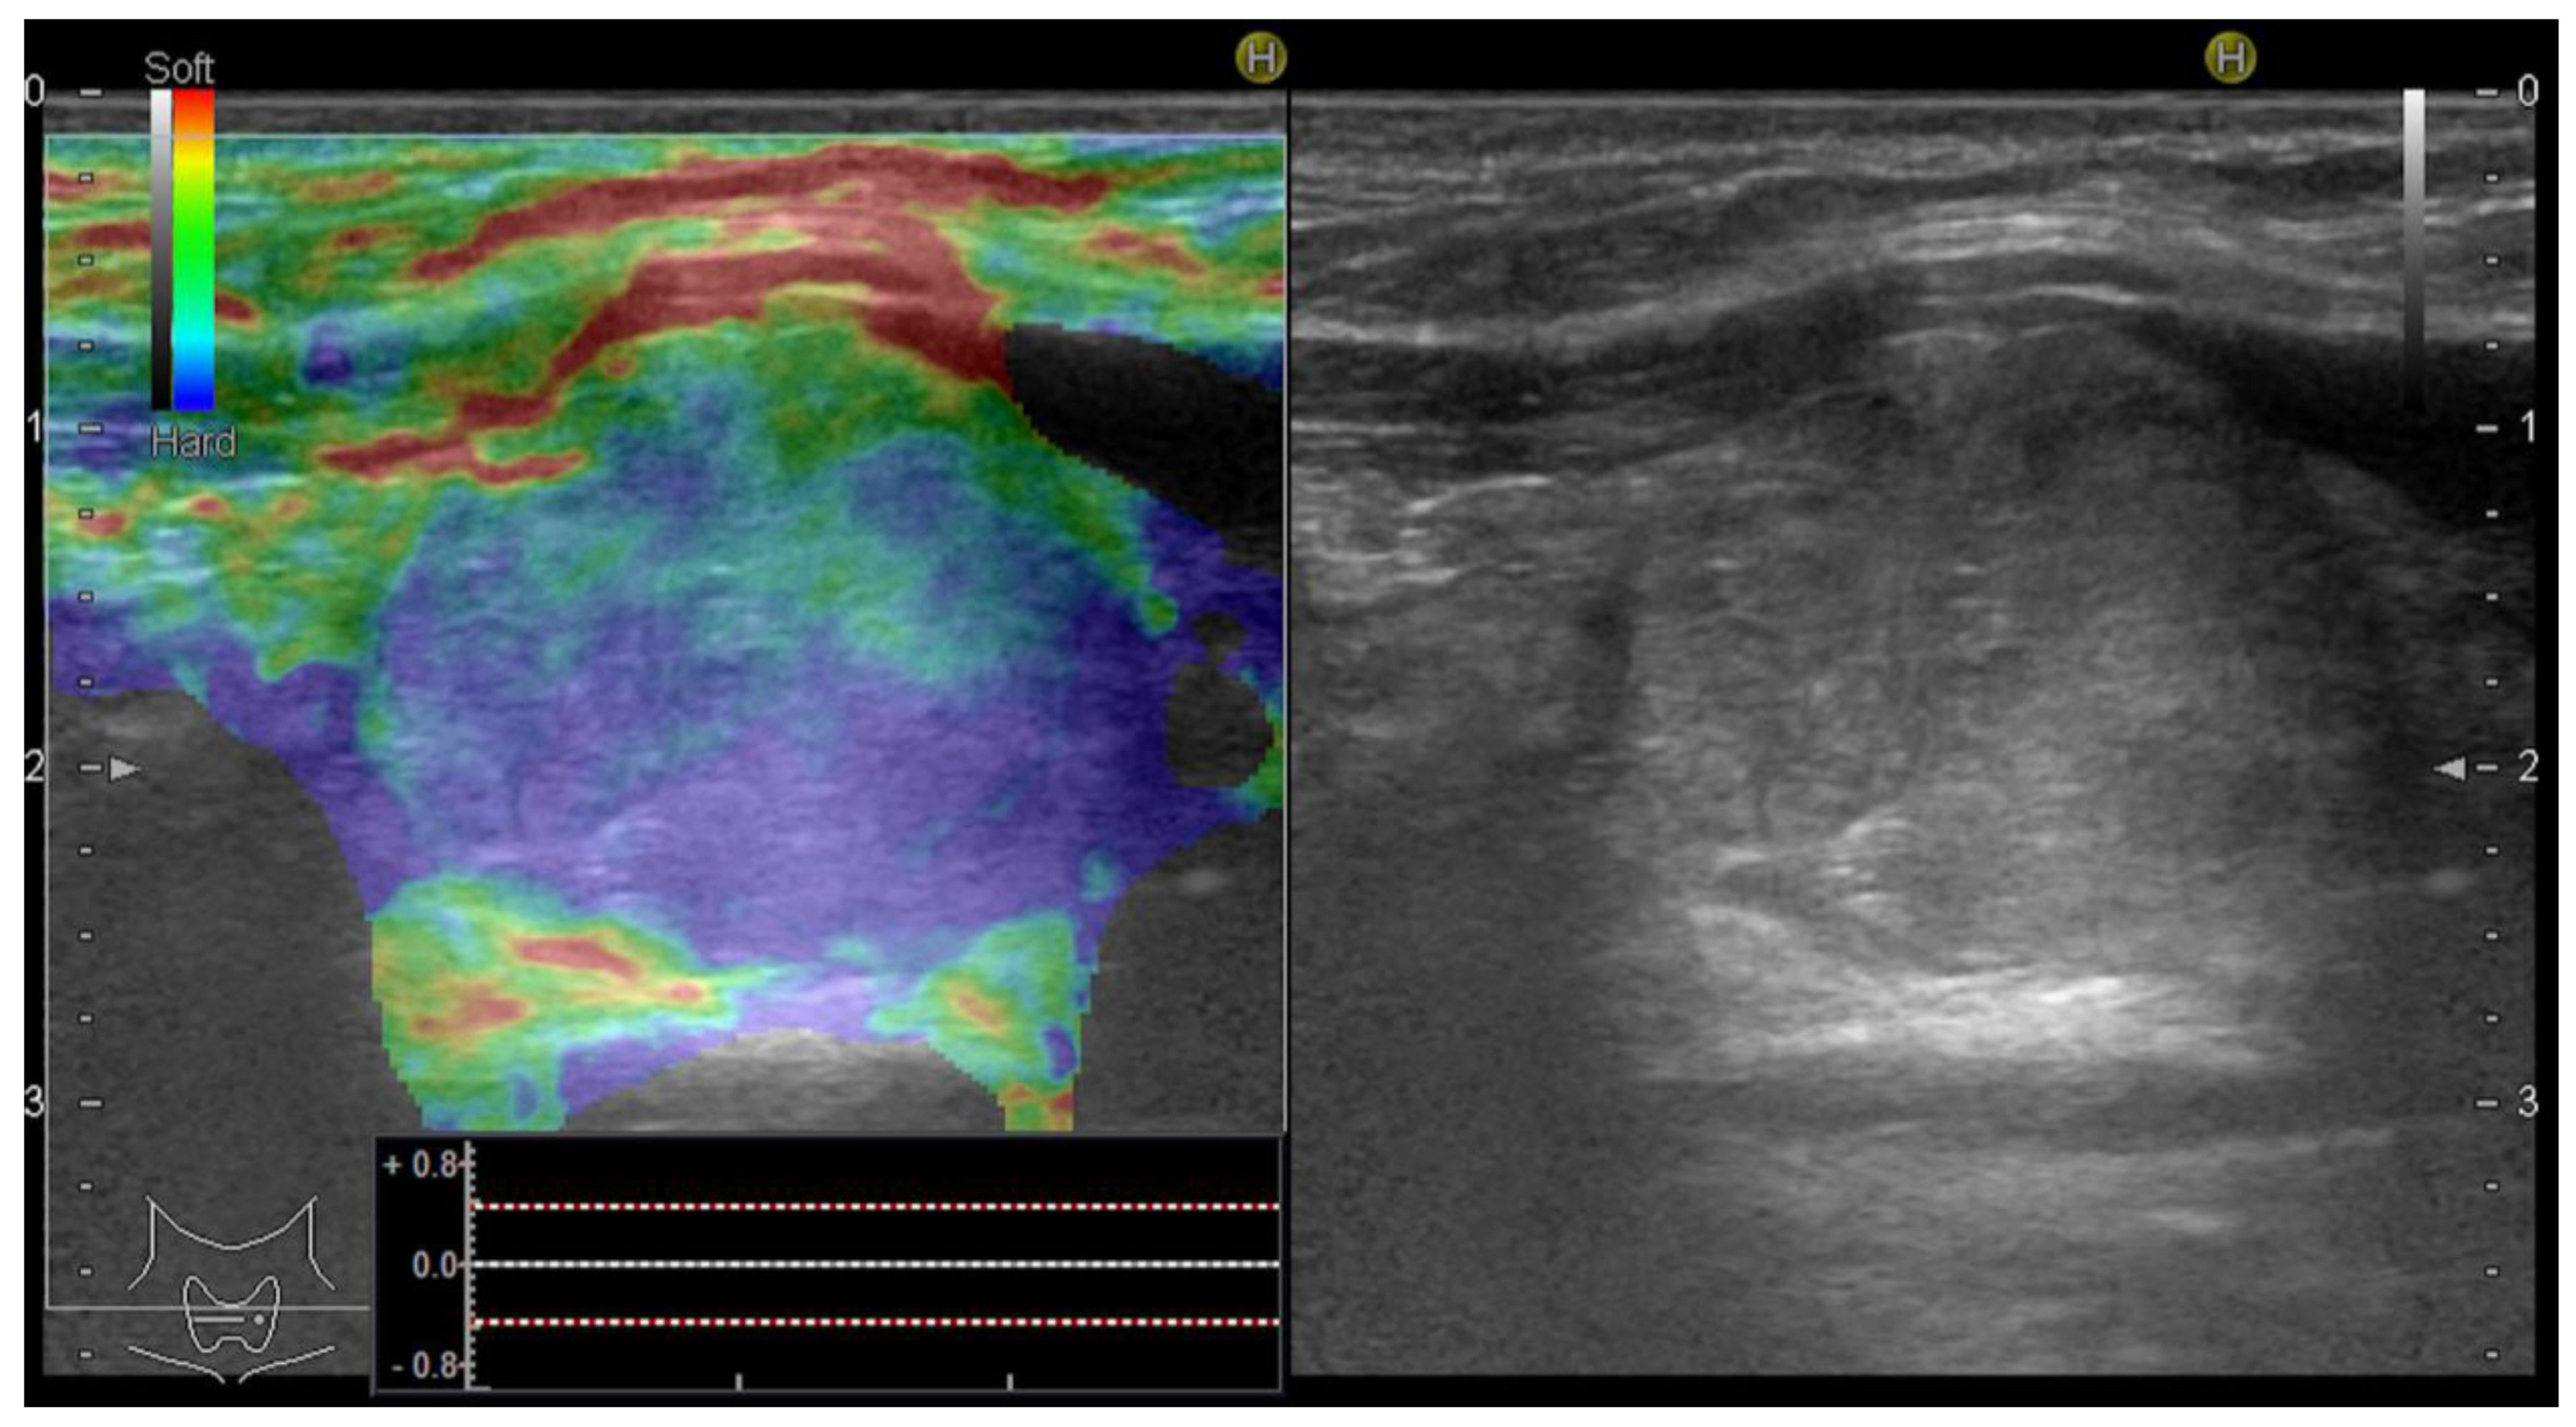

Firstly, the qualitative assessment was made based on the color map (red—soft tissue, green—intermediate stiffness and blue—hard nodules). The images were translated into a 1–4 score using the Asteria criteria, where 1 represents an entirely soft lesion; 2 represents a lesion that is mostly soft, with only a few spots of increased stiffness; 3 represents a lesion that is mostly stiff but with some soft spots; and 4, an entirely stiff one []. Nodules in categories 3 and 4 were considered as high risk [].

Additionally, an objective, semiquantitative evaluation providing a numeric value was also performed: the strain ratio, which shows the ratio between two ROIs that are located at similar depths, is called the parenchyma-to-nodule ratio, as exemplified in Figure 2. Longitudinal sections are preferred in order to obtain an image displaying enough surrounding healthy thyroid tissue []; in order to obtain longitudinal views, the probe is held parallel to the trachea to include the maximum length of the nodule in focus. In cases with associated autoimmune disease, when the elasticity of the surrounding parenchyma might be increased [], the semiquantitative ratio was not considered in the final analysis.

Figure 2.

Strain elastography (left) evaluation displaying a colormap overlaid on the greyscale image, Asteria score 4 (completely stiff/color blue); the nodule-to-parenchyma strain ratio (region of interest A covering the nodule and region of interest B in the healthy, adjacent thyroid parenchyma) displaying an increased value = 10.63 and the conventional ultrasound image (right) of a solid thyroid nodule.